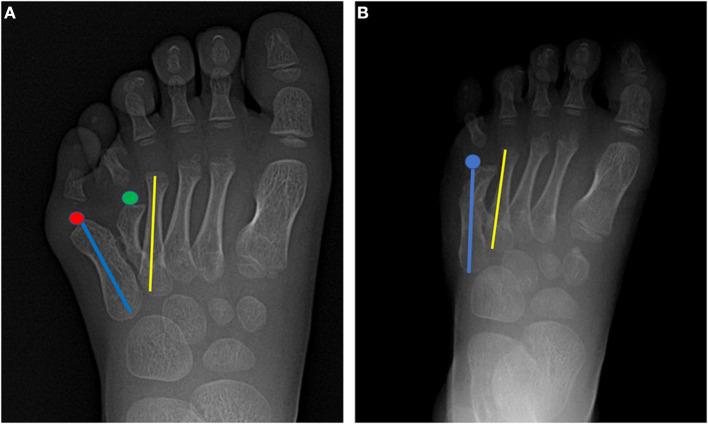

Polydactyly is a common deformity of the limbs, and excision of the extra digit has shown good results in the vast majority of patients. However, this treatment approach may not suitable for all cases of polydactyly. Some complex surgical procedures are required to treat rare forms of polydactyly and achieve satisfactory correction. Here, we report the use of on-top plasty technique for treating polydactyly between the 4th and 5th metatarsals with concomitant angulation of the 5th metatarsophalangeal joint. We performed the first osteotomy at the neck of metatarsal bone by "grafting" the distal polydactyly with the normal axis to the 5th metatarsal bone. Excision of the extra toe was accompanied by simultaneous restoration of the 5th toe axis and decrease in the width of the forefoot. Finally, both appearance and function could be improved. With this novel method, the complete osteoarticular structure and weight-bearing structure of foot were well-reconstructed. Based on the findings, we recommend that for the surgery of polydactyly, the beneficial parts should be preserved for reconstruction, and the tailored and personalized approach could be adopted.

多指畸形是一种常见的肢体畸形,绝大多数患者切除多余手指后效果良好。然而,这种治疗方法可能并不适用于所有多指畸形病例。治疗罕见类型的多指畸形并实现满意的矫正需要一些复杂的外科手术。在此,我们报告使用顶置成形术治疗第4和第5跖骨之间的多指畸形,并伴有第5跖趾关节成角。我们通过将具有正常轴线的远端多指“移植”到第5跖骨上,在跖骨颈部进行了第一次截骨术。切除多余脚趾的同时恢复了第5趾的轴线,并减小了前足的宽度。最终,外观和功能均得到改善。通过这种新方法,足部完整的骨关节结构和负重结构得到了良好重建。基于这些发现,我们建议对于多指畸形手术,应保留有益部分进行重建,并可采用量身定制的个性化方法。